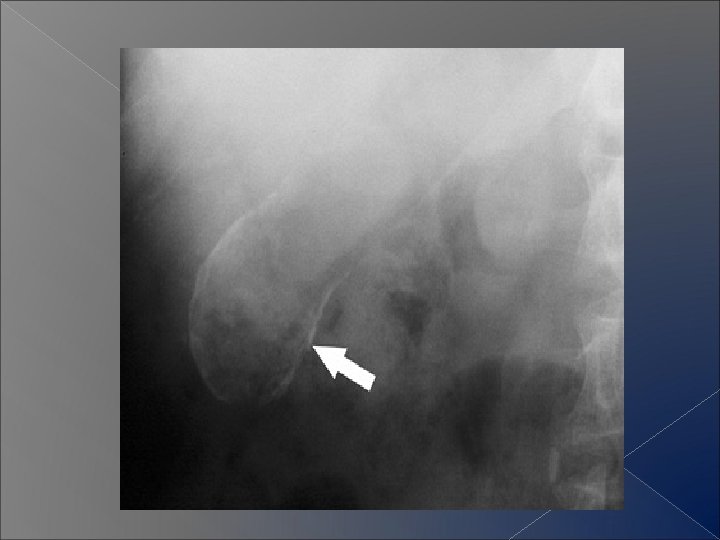

Abdominal calcification � Assess : Ø the location (two views) , Ø the pattern Ø the shape � Common calcifications

Patterns of abdominal alcifications � Rim like � Linear � Lamellar � Cloudy

Rim like calcification � Causes

Lamellar or laminar calcification � Causes

Amorphous or cloudy calcification